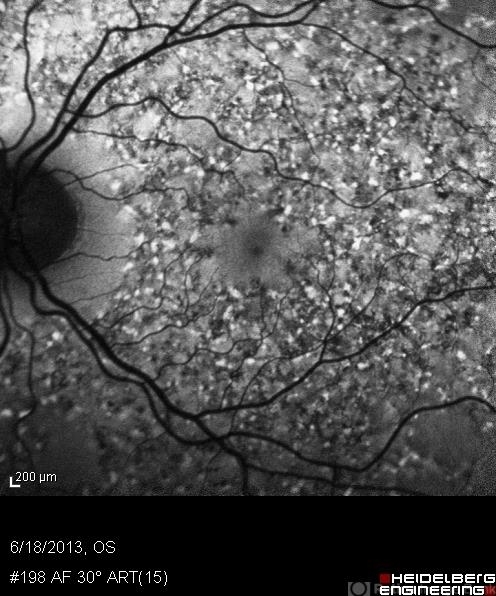

- Stargardt disease

- Charlotte Harris COA Midwest Eye Institute Indianapolis, IN

- Imaging device

- Heidelberg Spectralis

- FAF of a 30-year-old male with hereditary retinal dystrophy.